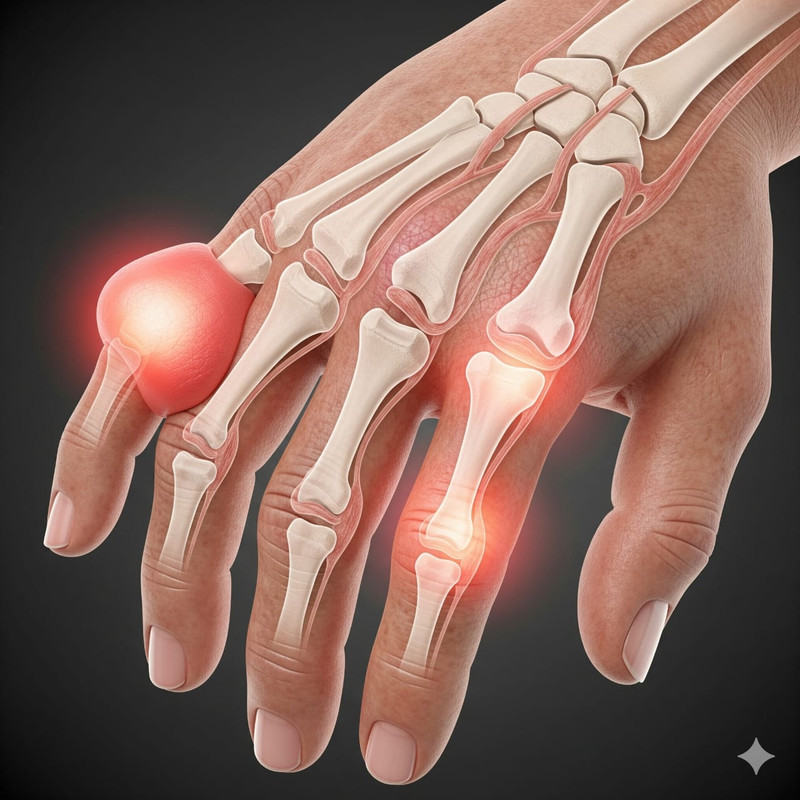

We also provide: Spondylitis (Kamar Dard), Arthritis (Ghutne ka Dard), Gastric problems, Gathia, Body pain massage, Piles, and handmade traditional medicines.